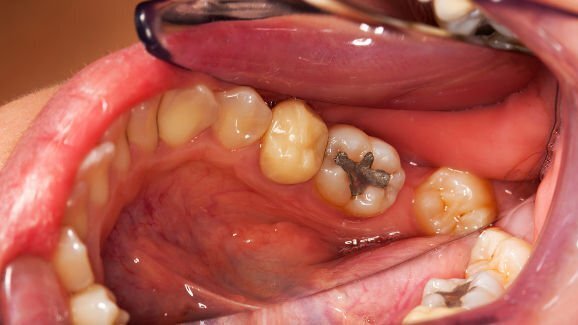

NOVA FRIBURGO, Brasil: A Universidade Federal Fluminense em Nova Friburgo, uma das maiores do país, faz história com a cerimônia de inauguração da primeira instalação de separadores de mercúrio de amálgama dentre as universidades brasileiras. Os separadores foram instalados para 95 cadeiras usadas por aproximadamente 400 estudantes de odontologia do programa da Universidade.

Dr. Claudio Fernandes, que tem lecionado para a Universidade nos últimos sete anos, supervisionou o projeto. Durante o último ano o Dr. Fernandes tem trabalhado com a Academia Internacional de Medicina Oral e Toxicologia (IAOMT - Academy of Oral Medicine and Toxicology) para implementar o descarte apropriado de amálgama e impulsionar a odontologia ao século 21.

Após participar do primeiro Programa de Assistência Técnica da IAOMT, no Rio de Janeiro em outubro de 2013, e aprender sobre ortodontia sem mercúrio, com manejo seguro de mercúrio e práticas ambientalmente seguras, ele solicitou ao IAOMT que apresentasse um workshop de um dia em sua Universidade, a fim de encorajar sua progressão pra implementação antecipada da Convenção de Minamata sobre mercúrio.